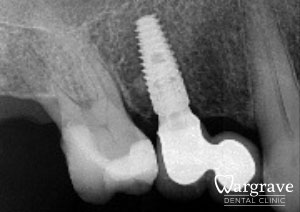

Healthy Smiles These are more advanced examples of different treatments available.All cases shown were carried out by Dr R Khurana unless otherwise stated. Immediate implants Anterior Mandible Bone Regeneration Anterior Mandibular Implant Bridge Maxillary Anterior Implant Bridge Implant stabilised ‘Life Like’ replacement dentures Implant Bridge after 10-years with zero bone loss Implant examples including ZBLC concepts Adhesive Bridge solution for a missing premolar Multidisciplinary care Orthodontics, Replacement veneers and composite bonding Adhesive Bridge solution for missing central incisors Replacement crown, Veneer and Composite Bonding Replacement Crowns and Veneer Injection Moulding using Composite Resin Equilibration Tooth Whitening to treat Developmental Discolouration